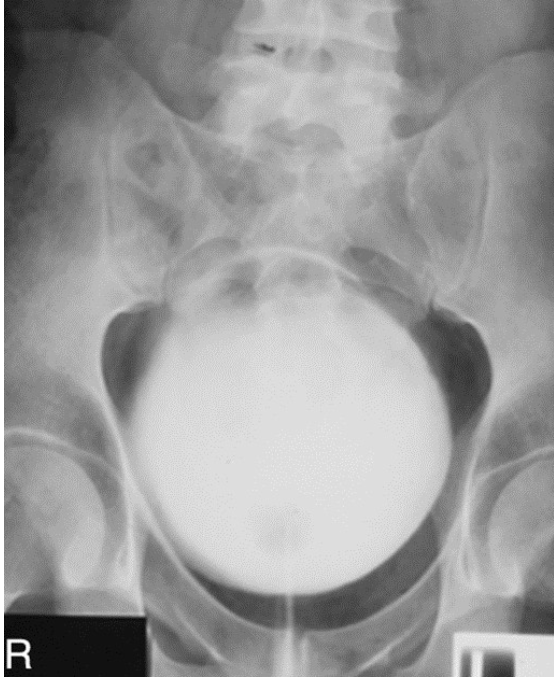

What contrast procedure was performed to produce this image?

VCUG – Voiding Cystourethrogram

NOT A cystography bc they are voiding in the image as shown by the line below of the urethra